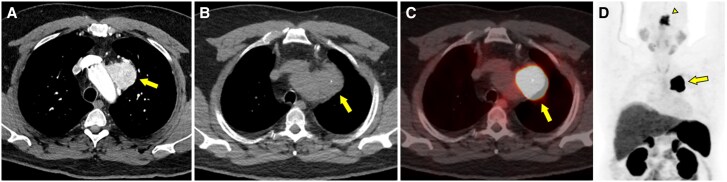

Prolactin-secreting pituitary adenomas are typically treated with dopamine agonists to inhibit prolactin secretion and reduce tumor size. Dopamine-secreting paragangliomas are rare neuroendocrine tumors of sympathetic and parasympathetic paraganglia and often do not provoke symptoms of catecholamine excess. Although overlapping genetic drivers have been described for paragangliomas and pituitary adenomas, biochemical crosstalk between coexisting tumors is underexplored. We describe the case of a 52-year-old male individual who presented with cerebrospinal fluid (CSF) rhinorrhea and was found to have an invasive, 4.2-cm pituitary mass with modestly elevated prolactin (130.9 ng/mL [130.9 µg/L], reference range [RR] 2-18 ng/mL [2-18 µg/L]). Additional imaging discovered a mediastinal mass suspicious for a thoracic paraganglioma. Biochemical screening demonstrated marked elevation of plasma and urinary dopamine. Following paraganglioma resection, dopamine levels normalized, but prolactin rose significantly (877.8 ng/mL [877.8 µg/L]), suggesting an endogenous dopamine agonist-like effect from the paraganglioma to suppress pituitary prolactin hypersecretion. Pituitary pathology was notable for a PIT1 (pituitary transcription factor-1)-lineage pituitary adenoma with absent immunohistochemical staining for prolactin. Genetic testing found a previously unreported germline SDHC variant of uncertain significance. In this case, we report a novel biologic signaling mechanism between 2 rare primary endocrine tumors and highlight challenges in their diagnosis and management.